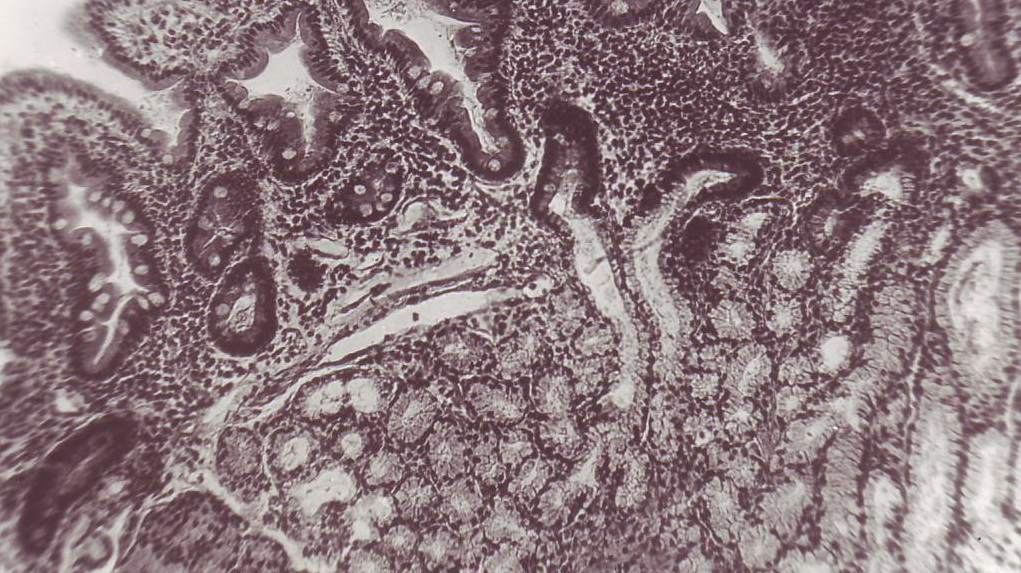

При

изучении биоптатов, полученных из параульцерозной зоны у больных

эрозивно-язвенными гастродуоденальными кровотечениями и ХОБЛ установлено, что

изменения носили распространенный характер, иногда с выраженной перестройкой

структуры слизистой оболочки. Желудочные ямки на большом протяжении извитые,

местами очень глубокие, заполненные секретом, чередовались с уплощенными ямками

мелкой глубины. В некоторых наблюдениях отмечались дистрофические изменения

клеток покровного эпителия со смазанными границами, с уплощенной формой,

наличием мелкозернистости и вакуолизации цитоплазмы, снижением интенсивности

окраски ядер. Нередко вследствие дистрофических изменений железистого эпителия

нарушалось слизеобразование. Покрывающий протекторный слой истончен. Ядра

смещались в апикальную часть клеток. Имело место нарушение слизеобразования.

Число желез в собственной пластинке слизистой оболочки было уменьшено, между

ними отмечались очаговые и диффузные разрастания соединительной ткани,

вследствие чего железы были разобщены, окруженные прослойками волокнистых

структур. Эти процессы сопровождались значительным отеком и разрыхлением

собственной пластинки. На фоне отека основного вещества стромы собственной

пластинки выявлялись расширенные, заполненные эритроцитами кровеносные сосуды с

явлениями стаза , что свидетельствовало о нарушении микроциркуляторного русла

(рисунок 1).

Рисунок 1 – Микрофото. Дистрофические изменения

покровного эпителия слизистой оболочки желудка (стрелки). Окр. Гематоксилином и

эозином. Ув.*200

Таким образом, наблюдаемые морфологические изменения в

слизистой оболочке желудка в большей степени зависят от циркуляторной гипоксии

вследствие нарушения микроциркуляторного русла, глубины дистрофических и

некротических изменений.